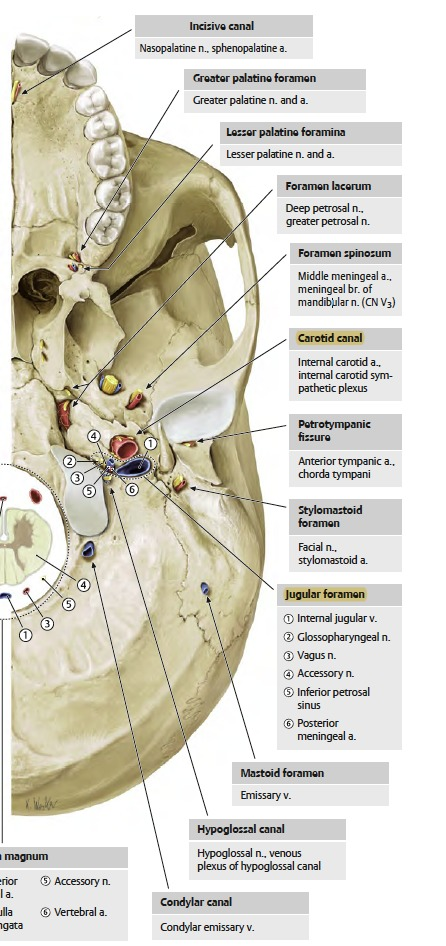

| CN | Origin | foramen |

|---|---|---|

| I | 嗅球 | cribriform plate |

| II | Optic Chiasma | optic canal |

| III, IV | Midbrain | sup orbital fissure |

| V1, VI | pons | |

| V2 | foramen rotundum | |

| V3 | foramen ovale | |

| VII | Internal coustic meatus | |

| VIII | Pons, Medulla 之間 | |

| IX, X, XI | Medulla | jugular foramen |

| XII | Hypoglossal canal |

Temporal bone

- Carotid canal

- Ext. acoustic meatus

- Int. acoustic meatus

- CN VII, VIII

- Jugular foramen

- int. jugular v.

- CN IX, X, XI

- Stylomastoid foramen

- Foramen lacerum

- Petrotympanic fissure

Occipital bone

- Hypoglossal canal

- CN XII

- Foramen magnum

- Spinal cord

- Vertebral a.

- CN XI

- Jugular foramen

- Foramen lacerum